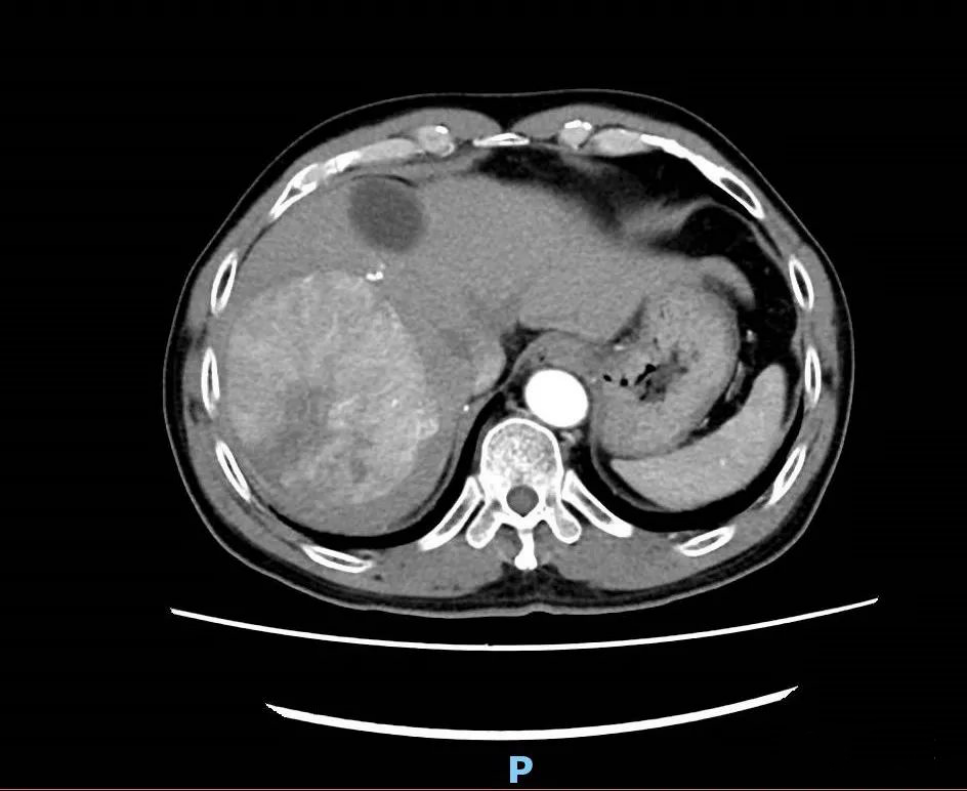

鉴于病人的情况特殊,为了减轻手术创伤,团队决定采取腹腔镜微创手术实施一期手术。手术团队依序实施腹腔镜下结扎门静脉右支、离断肝实质,手术十分顺利。两周后医生复查肝脏CT并评估肝再生情况,因残肝体积未达到二期肝切除标准,经过MDT团队讨论,给予介入、药物等治疗。1个月后,患者回到医院复查,经团队评估达肝切除条件,再次通过腹腔镜手术顺利切除右肝三叶。术后患者恢复良好,目前已康复出院。